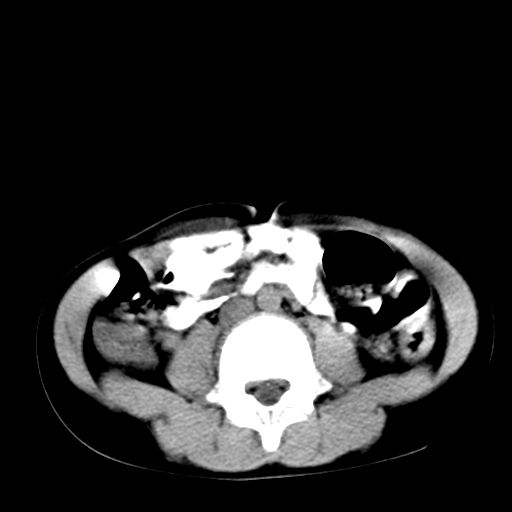

腹部好象未见异常。

腹部ct平扫未见明确异常

腹部ct平扫不能提示哪里有病变。